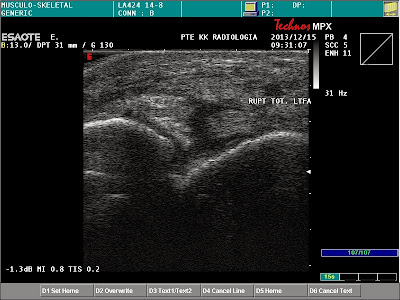

Rupture of the talofibuar ligament Szerző: admin | dec 15, 2013 | MSK | Nincsenek hozzászólások the ruptured LTFA is surrounded by mild hypoechogen area (haematoma) haematoma around the ruptured LTFA normal thickness and structure of LTFA Technos MPX is back!